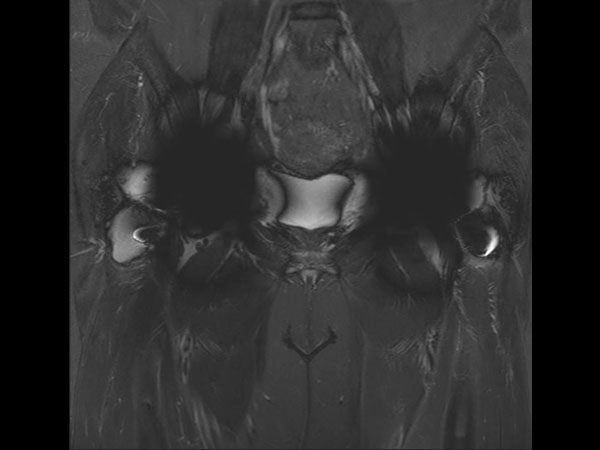

Coronal STIR TSE

Coronal STIR MARS